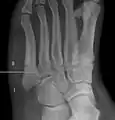

For several reasons, a Jones fracture may not unite. The diaphyseal bone (zone II), where the fracture occurs, is an area of potentially poor blood supply, existing in a watershed area between two blood supplies. This may compromise healing. In addition, there are various tendons, including the fibularis brevis and fibularis tertius, and two small muscles attached to the bone. These may pull the fracture apart and prevent healing.

Zones I and III have been associated with relatively guaranteed union and this union has taken place with only limited restriction of activity combined with early immobilization. On the other hand, zone II has been associated with either delayed or non-union and, consequently, it has been generally agreed that fractures in this area should be considered for some form of internal immobilization, such as internal screw fixation.

These zones can be identified anatomically and on x-ray adding to the clinical usefulness of this classification.[21] Surgical intervention is not, by itself, a guarantee of cure and has its own complication rate. Other reviews of the literature have concluded that conservative, non-operative, treatment is an acceptable option for the non-athlete.[22]

Anatomy of the fifth metatarsal.

3 zone description